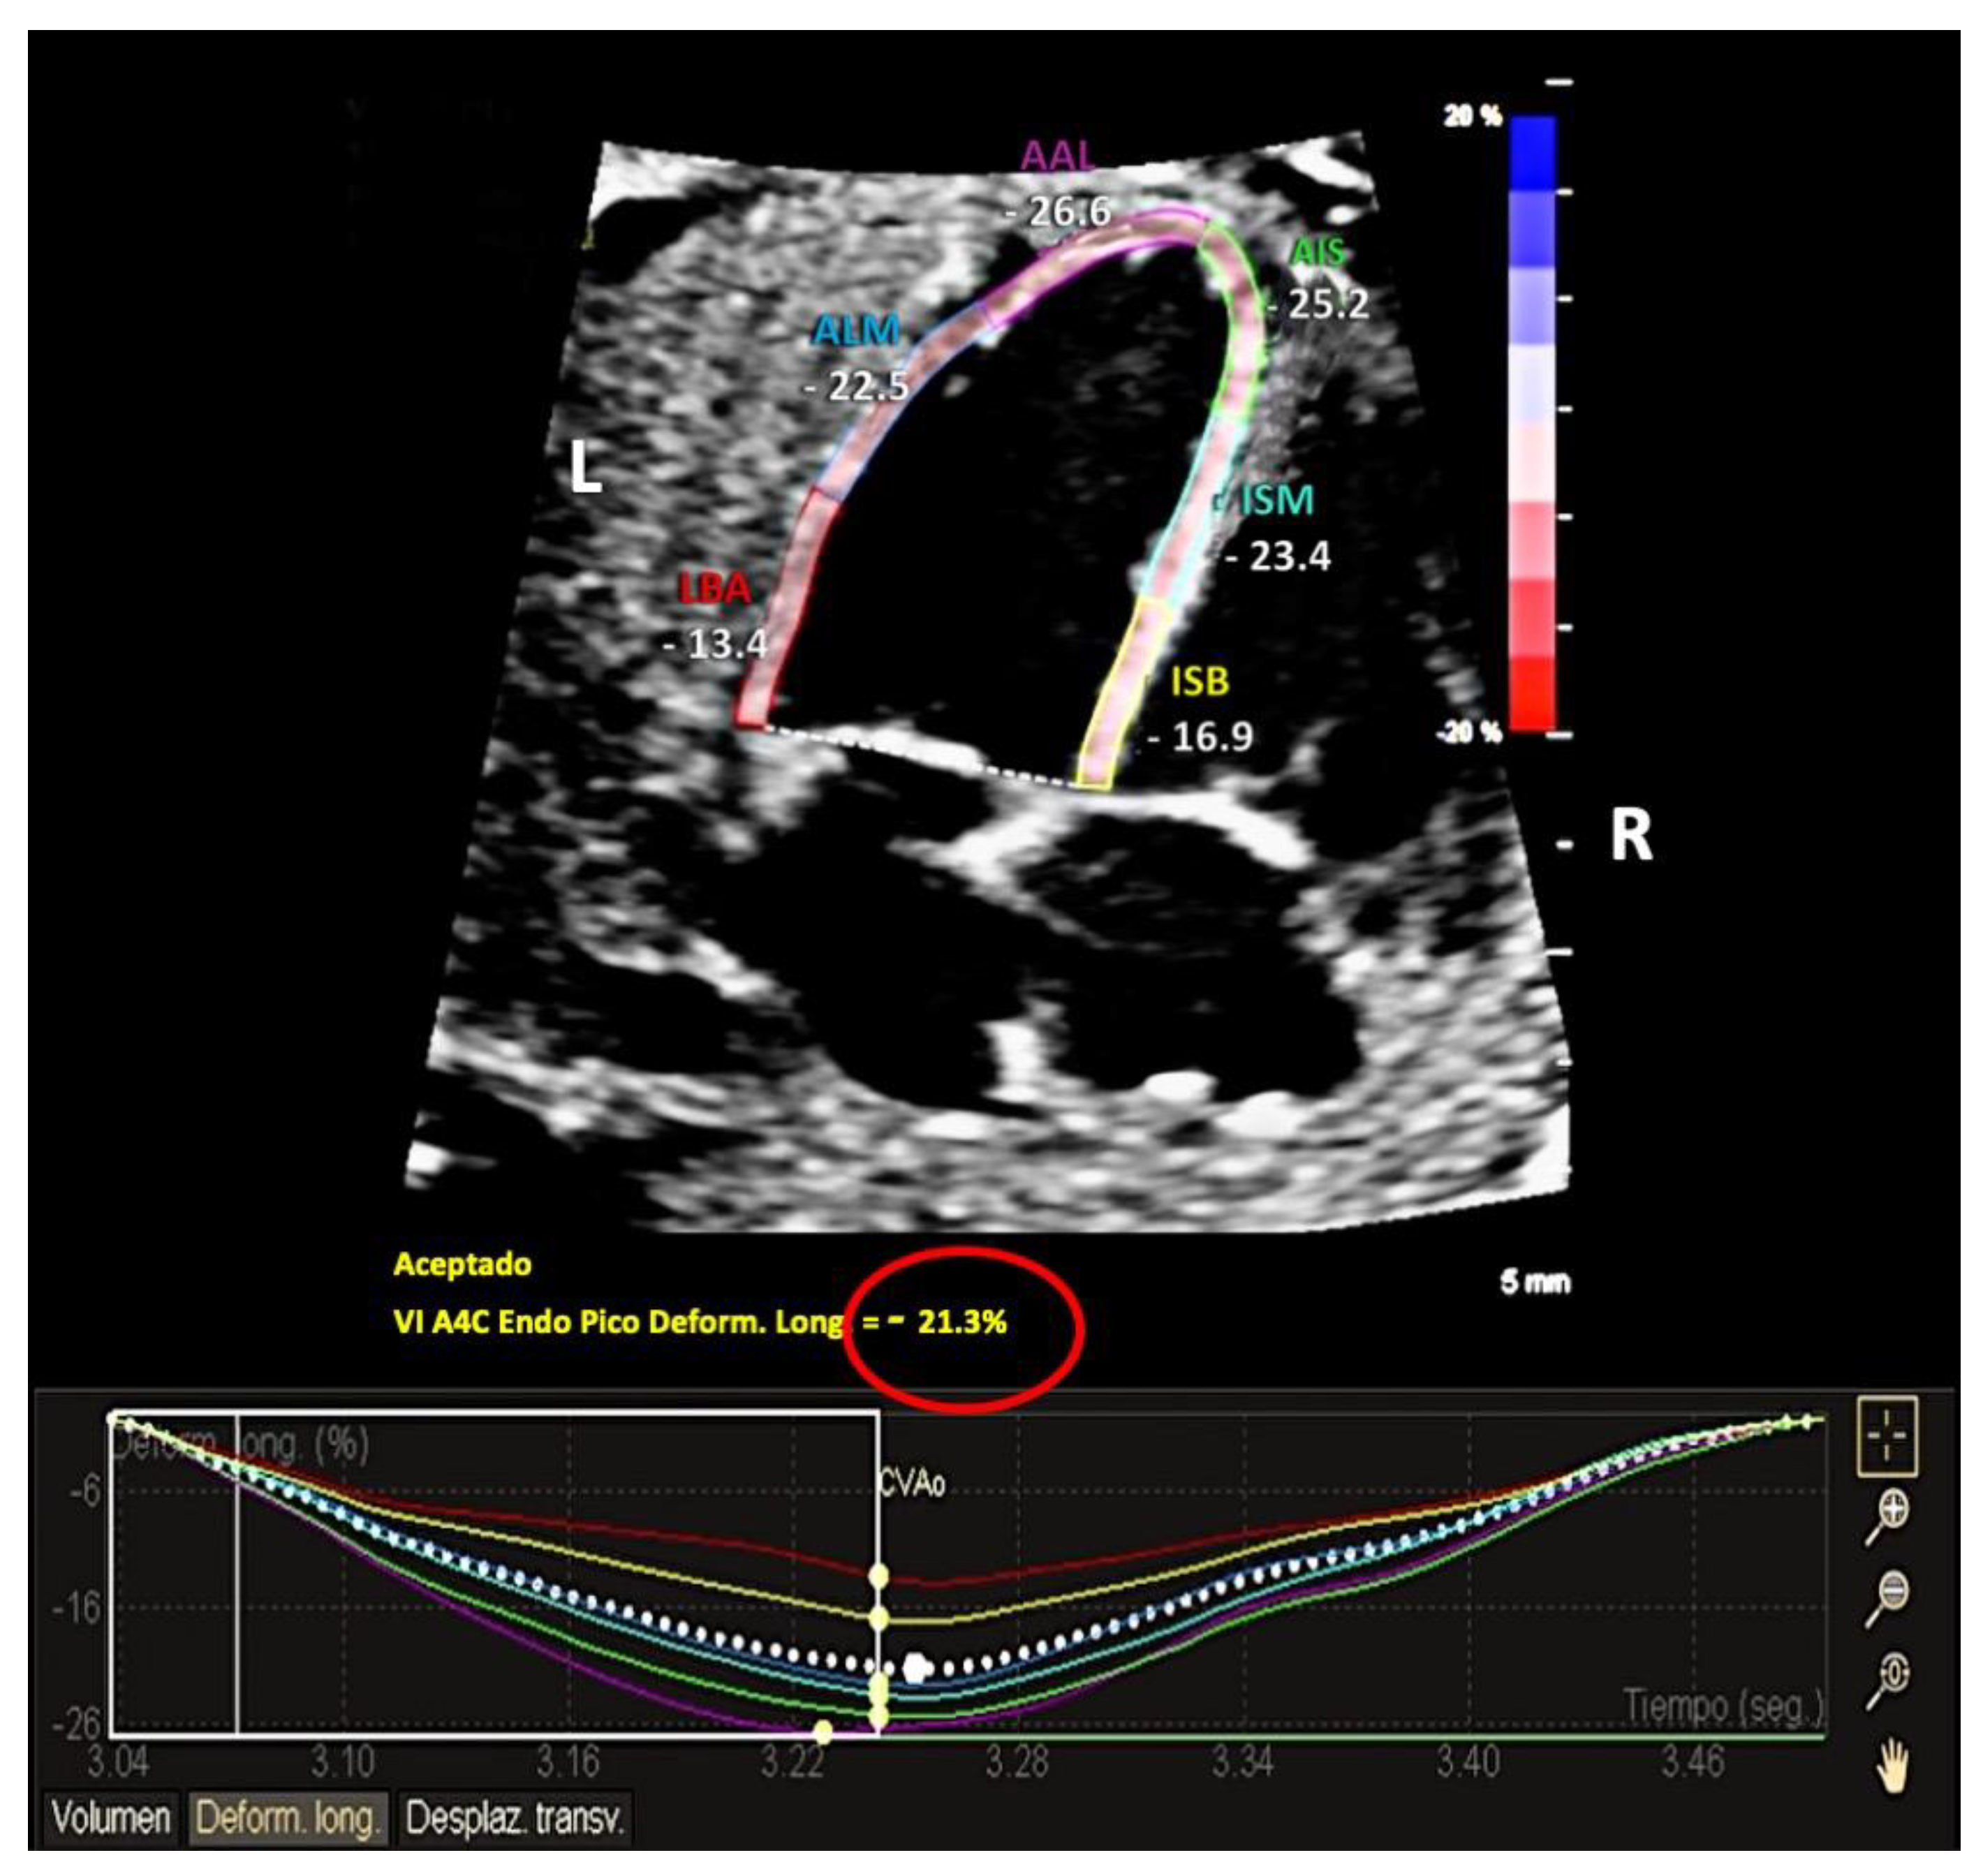

2.2. Ultrasound Acquisition

2.3. Analysis Protocol